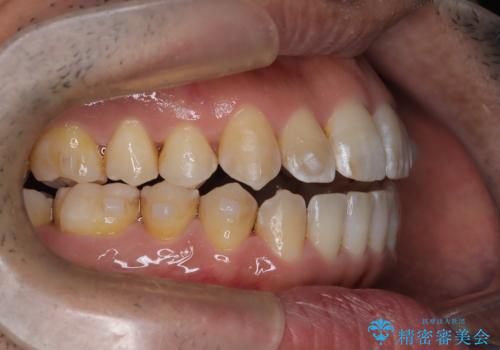

- 左上の八重歯を気にされて来院されました。精密な検査の結果、歯列全体を広げながら八重歯を奥へ移動させることで、美しい歯並びと機能的な咬み合わせが得られると診断。患者様のご希望に合わせ、透明で目立ちにくい**インビザライン(マウスピース矯正)**による治療計画を立案しました。抜歯を避け、歯を少しずつ遠心(奥)へ移動させることで、歯が並ぶスペースを確保し、叢生(歯のデコボコ)を改善します。

今回の矯正治療では、透明なマウスピース型の装置インビザラインを使用しました。この装置は目立ちにくく、取り外しが可能なため、食事や歯磨きも普段通りに行えます。遠心移動という方法で奥歯を後方に動かし、前歯を並べるためのスペースを確保。これにより、抜歯することなく、左上の八重歯を含む叢生を効果的に改善し、整った美しい歯並びと良好な咬み合わせを獲得していただけました。